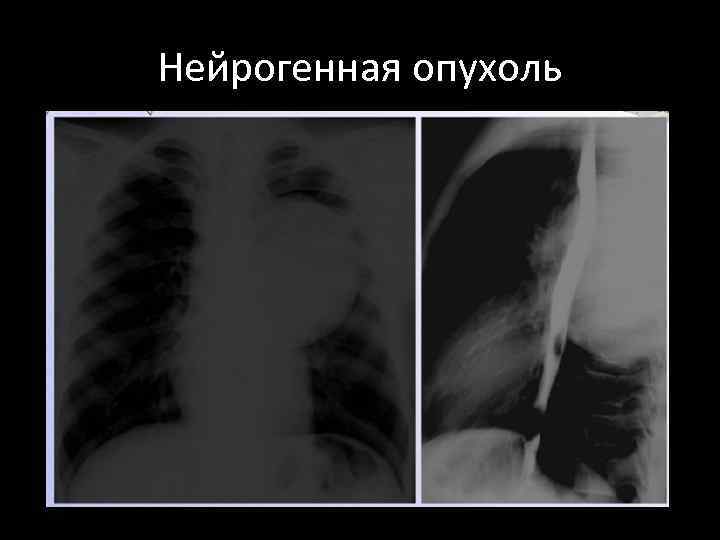

Нейрогенная опухоль

Семиотика нейрогенных опухолей • Полуокруглое или полуовальное образование • Располагаются паравертебрально, широким основанием примыкают к позвоночнику, • не отводится от позвоночника. • Контуры четкие, ровные иногда волнистые. • Структура однородная. • Большие опухоли могут сдавливать, смещать соседние органы, узурировать и разрушать прилежащие ребра и позвонки.

Нейрогенные опухоли • Могут происходить из всех нервных элементов средостения, но наиболее часто из пограничного симпатического ствола, корешков, оболочек спинного мозга, межреберных, блуждающего, диафрагмального, возвратного нервов. • Характерным клиническим симптомом является тупая, ноющая боль в груди и спине. • Дисфагия отмечается очень редко. • Чаще обнаруживается сколиоз. • При опухолях в виде песочных часов - радикулярные боли, парезы, параличи.